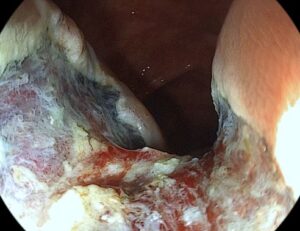

Εγκάρσιο :Επανελέγχεται η γνωστή επίπεδη πολυποειδής βλάβη διαμέτρου 4εκ., αφαιρέθηκε με βρόχο πολυπεκτομής μετά από υποβλεννογόνια έγχυση BluedeMethylene. Στη συνέχεια έγινε θερμοκαυτηριασμός στα ορατά αγγεία με Argon Plasma Coagulation (APC). Τοποθετήθηκαν 12 μεταλλικά αιμοστατικά clipsγια την σύγκλιση του ελλείματος και την αποφυγή μεταγενέστερης αιμορραγίας.